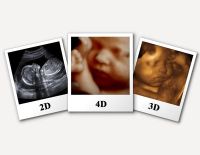

Tổng quan về siêu âm 3D và 7 câu hỏi thường gặp ở mẹ bầu

Siêu âm 3D là kĩ thuật siêu âm y khoa, sử dụng chủ yếu để chẩn đoán thai nhi, tim, hậu môn - trực tràng, mạch máu. Hiện nay, nhắc tới siêu âm, siêu âm 3D được người ta nói đến rất nhiều. Vậy nó...

Siêu âm 2D – Những thông tin mẹ bầu nên nắm bắt kịp thời

Siêu âm 2D là hình thức siêu âm dành cho các mẹ bầu ở những tuần đầu của thai kỳ. Đây là phương pháp siêu âm cũ nhưng vẫn được áp dụng nhiều hiện nay. Khi siêu âm 2D các mẹ bầu vẫn nắm được...